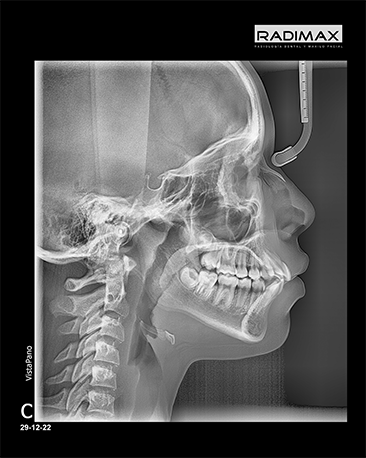

Perfil

Frontal (P-A)

Antero-posterior (AP)